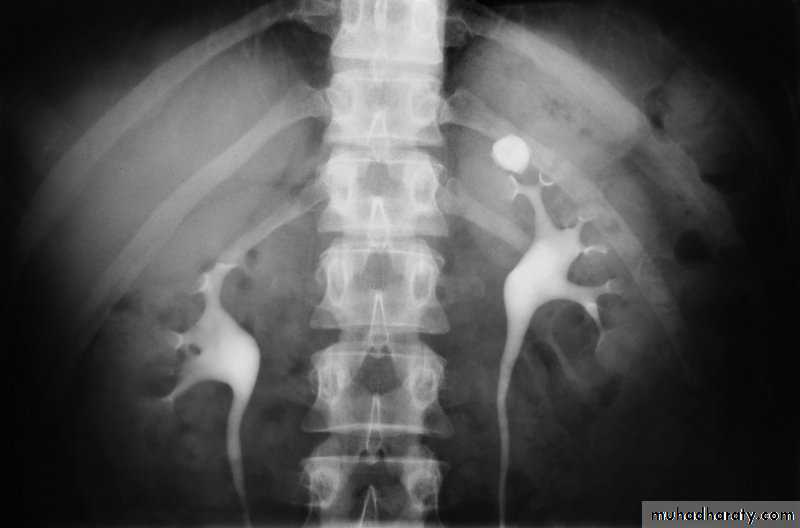

l.V.U. findings:

-Plain film may be useful in demonstrating calculi.

-After contrast injection:

Acutely obstructed kidney shows a dense nephrogram (dense opacification of the renal parenchyma).

excretion of contrast (opacification of the collecting system which may take many hours), then the level and degree of obstruction can be determined as dilated pelvi-caliceal system and ureter are followed down to the point of obstruction (point of hold up).

Pyeloxinus reflux may result from rupture of a fornix precipitated by contrast-induced diuresis superimposed on the increased hydrostatic pressure of an obstructed pelvicaliceal system. Urine and contrast extravasate into the renal sinus and perirenal space